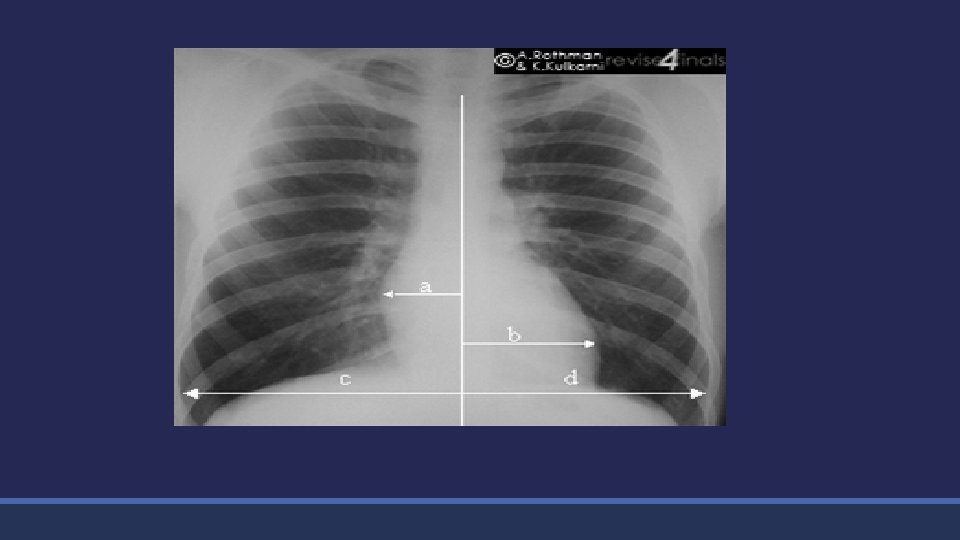

Chest X-ray